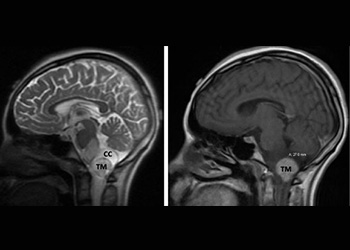

Brain:

74 Year Old Woman with Occipital Headaches

Author: Michael Brisman M.D., F.A.C.S., Read More!